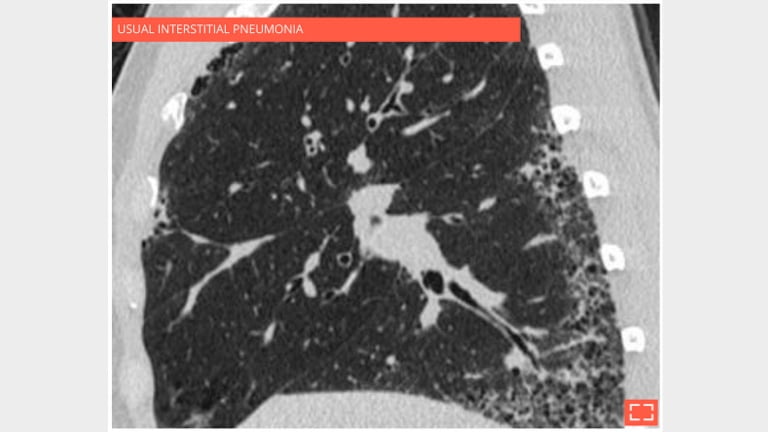

3. Honeycombing

honey-3

Sagittal reformation in the same patient showing the preferential subpleural and basal distribution.